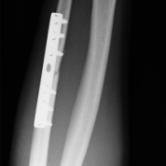

Röntgenbilder